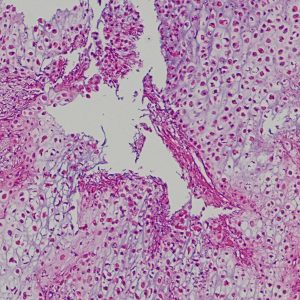

低悪性度軟骨肉腫の病理像 grade 2 chondrosarcoma

背景は好塩基性の軟骨基質(粘液状 myxoid,軟骨様 chondroid)です。好酸性胞体をもつ異型紡錘形ないし上皮様細胞が多結節状に増殖しています。細胞密度はやや高い部分もあり,核は濃縮され大小不同や2核の細胞も見られます。MIB-1 index 3%